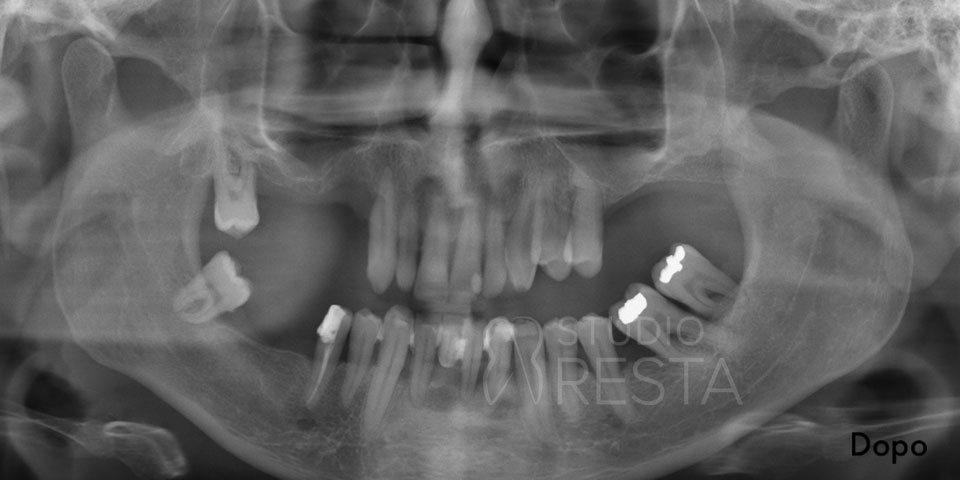

Prima di confermare la fattibilità di un impianto dentale All on Four, eseguiamo uno studio diagnostico approfondito. Presso il nostro studio, in un’unica seduta, realizziamo sia l’ortopantomografia digitale (radiografia panoramica) sia una TAC Cone Beam 3D a basse dosi, per valutare con precisione lo spessore e l’altezza dell’osso nelle varie zone dell’arcata. Questi esami ci permettono di pianificare l’intervento in dettaglio. In base alle immagini 3D, il dentista implantologo studierà la posizione ideale per ciascun impianto, evitando strutture delicate e massimizzando la stabilità.

- Esami diagnostici iniziali: prima dell’intervento effettuiamo in studio tutti gli esami radiografici necessari. Oltre alla classica radiografia panoramica (OPT), realizziamo una TAC Cone Beam 3D per studiare tridimensionalmente l’osso residuo. Questi esami guidano la pianificazione e garantiscono che l’intervento sia sicuro e senza sorprese.

- Controllo radiografico finale: a completamento dell’intervento, eseguiamo una radiografia di controllo (OPT) per verificare l’esatto posizionamento dei quattro impianti. Spesso si noterà che i due impianti posteriori sono inclinati verso la parte posteriore dell’arcata (tilted implants), confermando il caratteristico assetto “a V rovesciata” dell’All on 4.